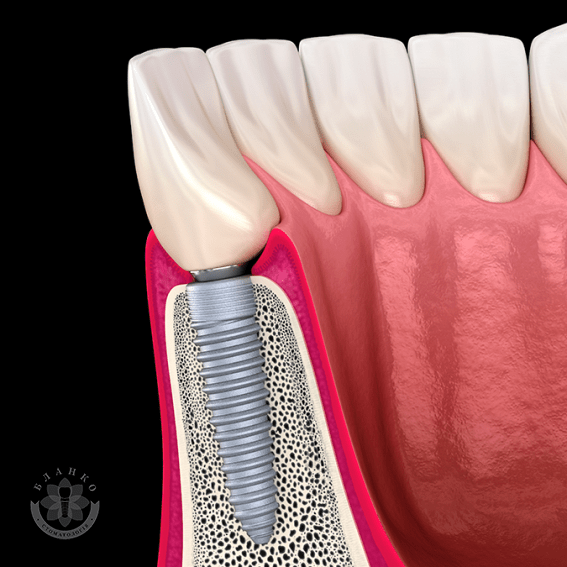

Зубная имплантация — это современное и надежное решение для восстановления утраченных зубов. В стоматологической клинике Бланко мы предлагаем имплантацию зубов «под ключ», что означает полный комплекс услуг — от диагностики до установки коронки, без скрытых платежей и неожиданных расходов.

🔹 Высококачественные импланты – используем только проверенные бренды, которые служат десятилетиями.